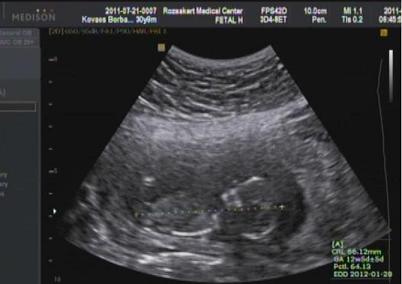

A baba 66, B baba 69mm volt. Tarkóredőjük is OK.

B baba jobban látható volt, sajnos A babánál a szív egyes részei nem látszódtak megfelelően mert nagy a "hájam" + a mellső méhlepény is rontott a helyzeten, de úgy néz ki,h nála is minden OK. A vérvételnek holnap lesz eredménye...remélem nem romlik a mostani biztató helyzet :roll: Elekes doktor nagyon cuki volt pláne a végén. Látta a férjemen,h egy kicsit szontyi és kérdezte,h mi a baj. Erre a férjem könnyes szemmel mondta,h még eddig nem tudtunk örülni...és olyan jó dolgokat mondott Elekes doktor,h a végén azért sírtunk :oops: Szóval jó élmény volt, de nagyon fárasztó. Nem is gondoltam volna...kicsit több mint másfél órát vizsgált :shock: nagyon alapos volt.

Kaptunk videót meg képeket. A videóból szedtem ki egy-egy képet és egy közöset :lol:

A baba :P

Kép

B baba :P

Együtt :P